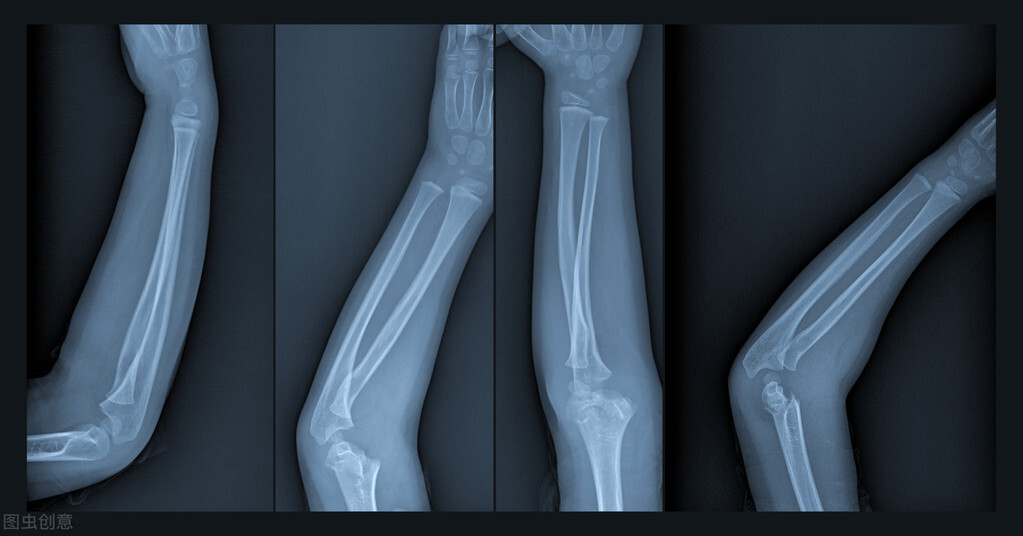

手术以后可以去医院复查三、四次,但是不能常去拍片子(不是说不能拍X光片,要适当、尽量减少拍片的次数),不然对骨折的愈合有碍!具体是否已经骨折愈合,最终要经过拍片决定,还要结合临床检查!

骨折的临床愈合标准

1、骨折局部无压痛以及纵向叩击痛;

2、局部无反常活动;

3、X线片示骨折线模糊,有连续骨痂通过骨折线;

4、外固定解除以后,上肢能满足以下要求:上肢能向前平举1KG重量达一分钟;下肢能在平地、不扶拐的情况下连续步行3分钟,并不少于30步;

5、连续观察两周骨折处不变形。